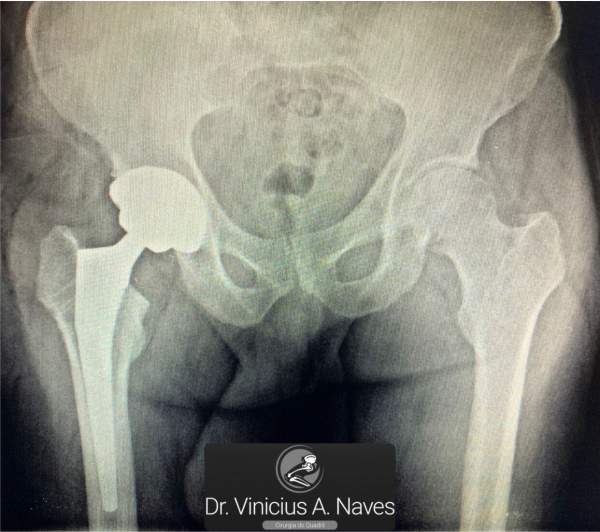

Prótese Total de Quadril

A artroplastia do quadril consiste na substituição da articulação doente. Está indicada mais frequentemente em artroses do quadril e nas fraturas do colo femoral em pacientes com idade mais avançada.

Há diversos modelos de próteses no mercado, mas no geral podem ser divididas da forma em que se fixam no osso em não cimentadas e cimentadas (com utilização de cimentos ósseos). Também são divididas de acordo com o material de seus componentes: metal-polietileno, cerâmica-polietileno, cerâmica-cerâmica, cada qual com sua correta indicação.

A via de acesso para realizar a cirurgia pode ser posterior, lateral ou anterior à articulação. Todas com excelentes resultados a depender da experiência do cirurgião com determinada via de acesso.

A cirurgia costuma trazer grande satisfação com melhora da dor e da função e a recuperação total costuma ser rápida em torno de 4 meses, mas é muito dependente de cada paciente.

A artroplastia total do quadril foi considerada “A Cirurgia Ortopédica do Século XX” pela revista The Lancet em 2007 devido a sua enorme revolução em relação ao tratamento da artrose do quadril.

A correta indicação, via de acesso, tipo de prótese, cirurgia, recuperação, riscos e expectativas devem ser discutidos detalhadamente antes da cirurgia na consulta com seu cirurgião.